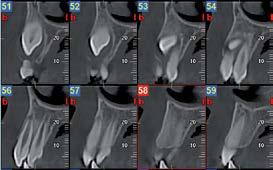

L’innovazione e la sicurezza sono due dei valori perseguiti dallo Studio Braconi a Terni, un punto di riferimento nell’ambito della radiologia 3D ortopedica grazie alla presenza del macchinario Newton 5G XL: si tratta dell’unico apparecchio nel Centro Italia che permette di eseguire una perfetta diagnostica per immagini in ortopedia e per la cervicale, oltre per le piccole articolazioni come seni paranasali, orecchie, colonna cervicale, gomito, polso, mano, ginocchio, caviglia e piede.

Nell’ambito della radiologia 3D ortopedica, il centro diagnostico utilizza il nuovissimo macchinario NewTom 5G XL, in grado di individuare con la massima precisione la presenza di fratture o lussazioni delle articolazioni, controllare la corretta guarigione di una frattura, valutare una lesione o una ferita causata da infezione, artrite o crescita anormale dell’osso.

Il tutto mediante una semplice e veloce scansione, grazie alla quale si otterranno diverse immagini in 3D ad altissima risoluzione e, per ottenere immagini ancora più nitide mediante un bassissimo dosaggio di radiazioni, gli esperti si avvalgono dell’innovazione racchiusa nella tecnologia Cone Beam.

Se con la radiologia tradizionale era necessario eseguire scansioni multiple, la novità introdotta dal macchinario NewTom 5G XL risiede nella capacità di fornire immagini ad alta risoluzione in un’unica scansione, mostrando nitidamente i dettagli delle articolazioni degli arti superiori e inferiori. Inoltre, a differenza della tecnologia 2D, la radiologia 3D ortopedica permette di individuare immediatamente alcune patologie come quella del metatarso, la quale richiede un allineamento visivo dedicato o una diagnosi delle micro fratture ossee.